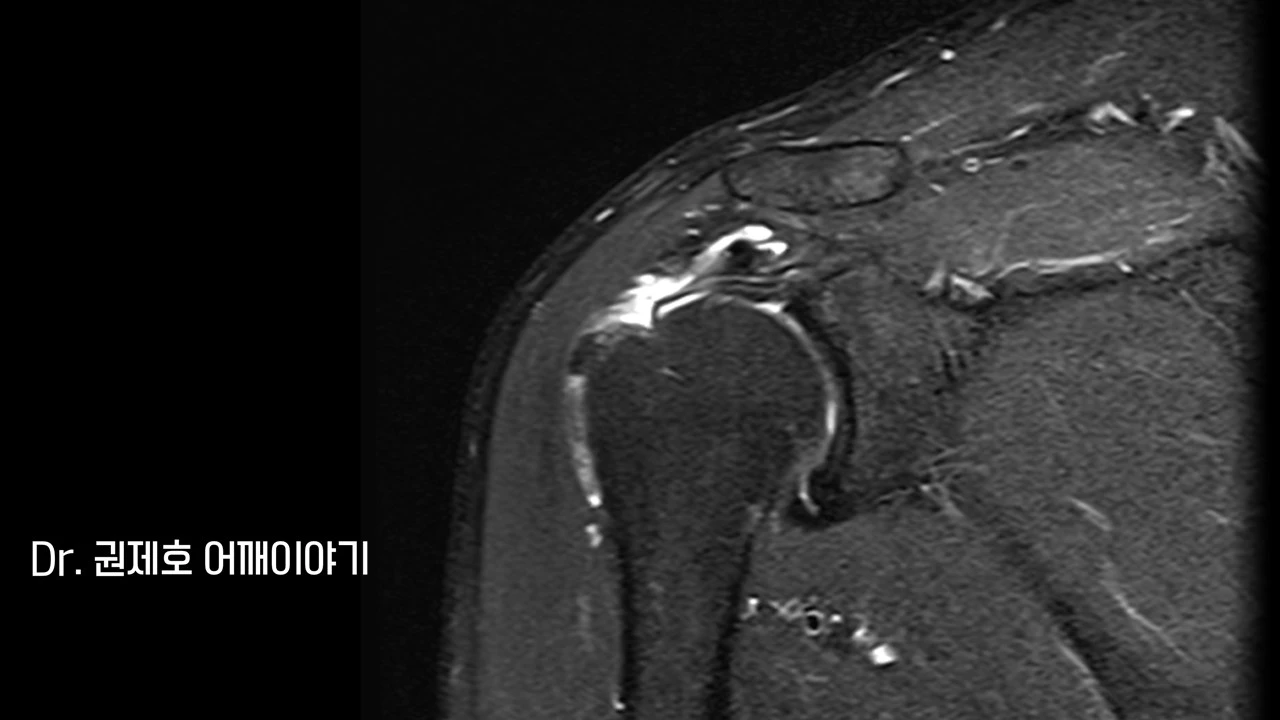

어깨 MRI를 검사하는 이유는 어깨 주변을 객관적으로 판단하기 위함이다. 거의 100장에 가까운 사진을 이 각도, 저 각도에서 찍고, 이를 모두 한꺼번에 보면서 판독을 하는데, 가장 대표적인 사진 한 장 만을 추렸다.

MRI에서 보면 회전근개 (어깨 인대)가 끊어지면서 속으로 말린 현상이 보였으며, 끊어진 부위는 헤진 상태였다.